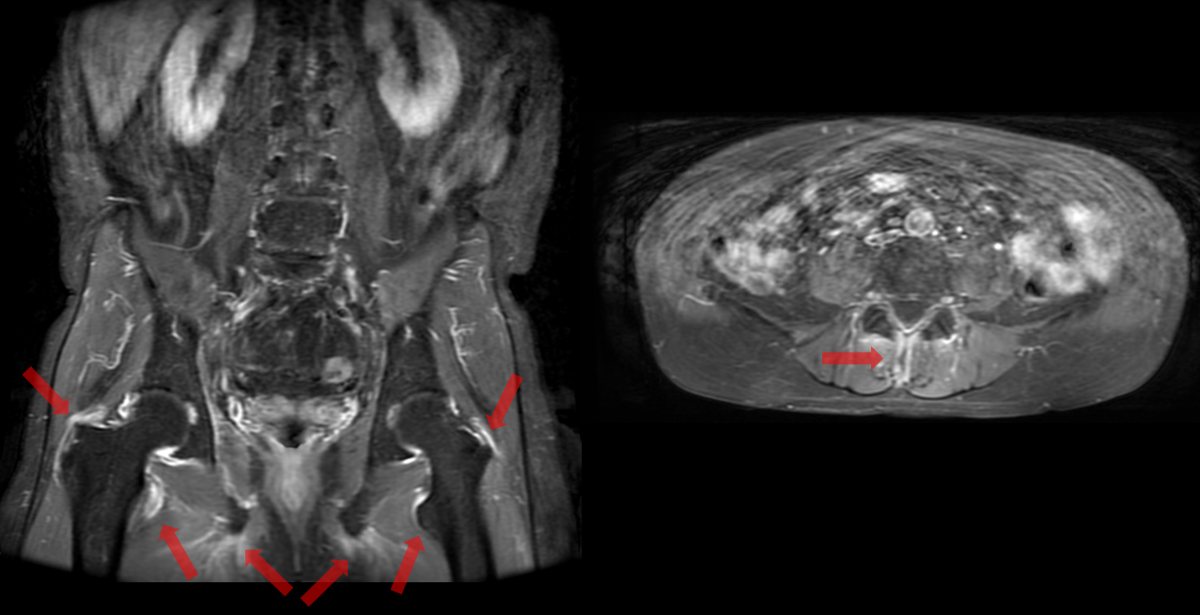

- 造影後T1強調像

大転子、小転子、坐骨結節、棘突起に造影効果

- 【椎体の後方成分にも注目】

脊椎炎では、椎体の変化だけではなく、肋椎関節、椎間関節や棘突起にも炎症が起きる。